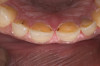

A 20-year-old male patient presented with irregular upper anterior teeth and was unhappy with his smile (Figure 4). He complained of occasional generalized mild sensitivity. Dental treatment history revealed that he had occasional dental work done in the past. Two weeks previously, he had severe pain in tooth No. 10, which was treated endodontically, and he was then referred to the author’s practice for management of anterior wear. Tooth No. 3 had a broken amalgam restoration.

Examination revealed that palatal surfaces of teeth Nos. 6 through 11 showed severe loss of tooth structure, with mild wear on the lower incisors and loss of anterior guidance (Figure 5 through Figure 7). The palatal TSL was consistent with the clinical picture presented by patients with gastric reflux. A detailed medical history was taken, and the patient complained of having heartburn and acidity at least 4 out of 7 days a week. He had never sought treatment for it and used over-the-counter medication when needed. He was a nonsmoker, with occasional intake of alcohol. He had a high-stress job with irregular meal times. A thorough smile and dental analysis11 was carried out; the findings appear in Table 2.